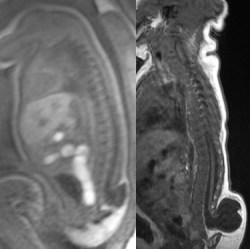

sur l’IRM, on identifie la moelle épinière qui se continue dans une poche liquidienne dont la paroi est constituée d’une lipome volumineux

il s’agit d’une forme kystique de myélolipome terminal. la moelle se termine en trompette, s’épanouissant au fond de la poche kystique. cette poche se continue par un lipome sous-cutané, l’ensemble est de volume variable, parfois majeur. des racines récurrentes partent du fond de la poche méningée et se terminent soit plus haut latéralement dans la dure-mère, soit remontent jusqu’au foramens radiculaires.

il peut s’y associer une cavité syringomyélique qui témoigne d’une souffrance médullaire.